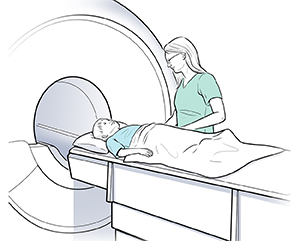

MRI. This test uses a combination of large magnets, radiofrequencies, and a computer to make detailed images of organs and structures within the body. Certain metals can't be used with the magnets in an MRI scanner. Discuss the risk of any implanted devices or hardware with your child's healthcare provider. Also tell the radiology staff. Sometimes your child will need to remove braces or dental devices before an MRI. Talk with your child's provider to find out if this is needed. MRI studies take longer than CT, and the machine makes a lot of noise. Young children may need to have sedation so that they can stay still throughout the MRI exam. MRI has no radiation exposure.